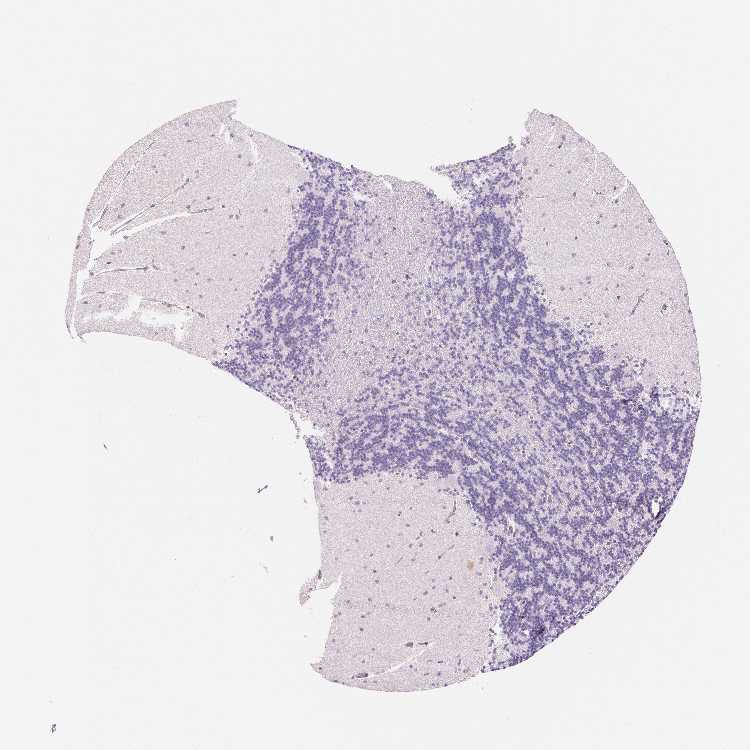

CEREBELLUM - Antibody stainingi

Antibody staining in the annotated cell types in the current human tissue is reported as not detected, low, medium, or high, based on conventional immunohistochemistry profiling in selected tissues. This score is based on the combination of the staining intensity and fraction of stained cells.

Each image is clickable and will lead to virtual microscopy that enables deeper exploration of all samples and also displays staining intensity scores, fraction scores and subcellular localization as well as patient and tissue information for each sample.

Antibody HPA051778Antibody HPA058590Antibody CAB001721

Purkinje cells Not detectedNot detectedNot detected

Cells in granular layer Not detectedMediumNot detected

Cells in molecular layer Not detectedNot detectedNot detected